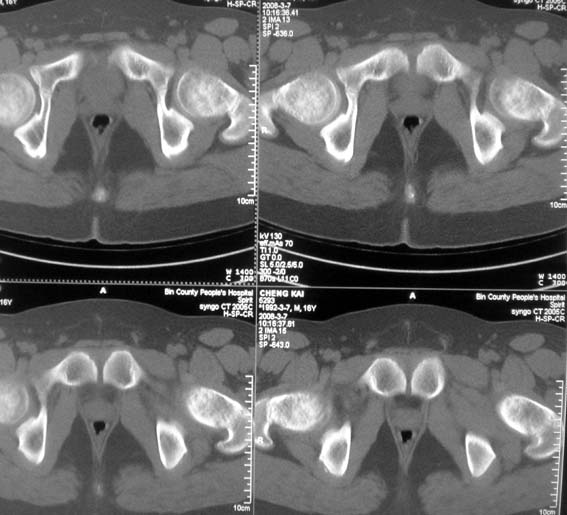

男,16岁,髋部疼痛,发育延迟。

考虑:双侧髋臼发育不良性骨病。

双侧髋臼发育不良性骨病

双侧髋臼发育不良性骨病.股骨头早期坏死?

双侧髋臼发育不良性骨病(髋臼窝变浅,髋臼内上缘关节面毛糙)。

考虑:双侧髋臼发育不良性骨病